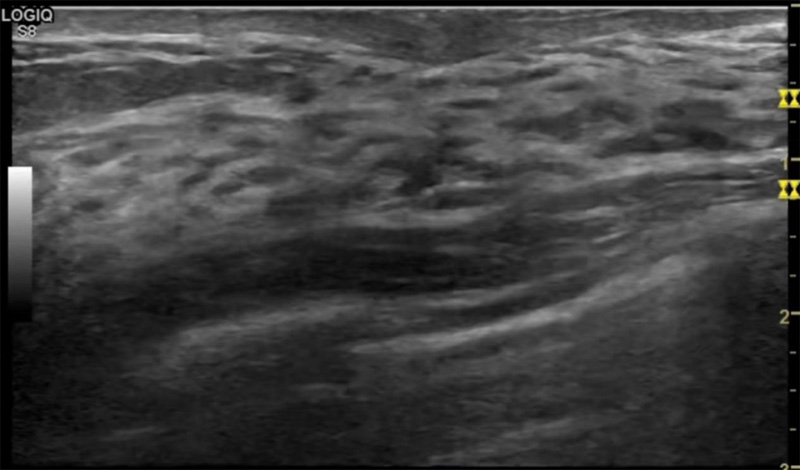

乳房脹痛,觸摸疼痛,手摸起來(lái)感覺有腫塊。這個(gè)是什么問(wèn)題呢?醫(yī)生診斷一般是乳腺增生。那么在乳腺超聲設(shè)備檢查后,報(bào)告單卻顯示雙乳未見明顯占位性病變。乳腺增生是很多女性,特別是育齡期女性都有的經(jīng)歷、到底乳腺增生癥狀有哪些?會(huì)給我們帶來(lái)怎樣的影響呢?乳腺增生不是腫瘤跟炎癥。乳腺組織增生及退行性變跟內(nèi)分泌功能紊亂有關(guān)系。正常的生理改變。還有乳腺病,良性乳腺結(jié)構(gòu)不良等名稱。

乳腺增生有什么癥狀,病因?比較典型的就是乳房疼痛,特別是經(jīng)前癥狀比較重,經(jīng)后就有所緩解。有時(shí)候還能碰到乳房硬塊。根據(jù)經(jīng)期的變化而變化硬度大小都有變。乳腺在內(nèi)分泌激素,伴隨月經(jīng)周期有增生問(wèn)題。內(nèi)分泌激素代謝失衡,雌激素水平增高,出現(xiàn)乳腺組織增生過(guò)度,增生組織不退的情況下,就會(huì)有乳腺增生癥狀。這個(gè)不會(huì)增加乳腺癌的風(fēng)險(xiǎn)。所以不用緊張的。不過(guò)乳腺癌的病人都會(huì)有乳腺增生。所以乳腺增長(zhǎng)有沒癥狀,都需要進(jìn)行常規(guī)的體檢。